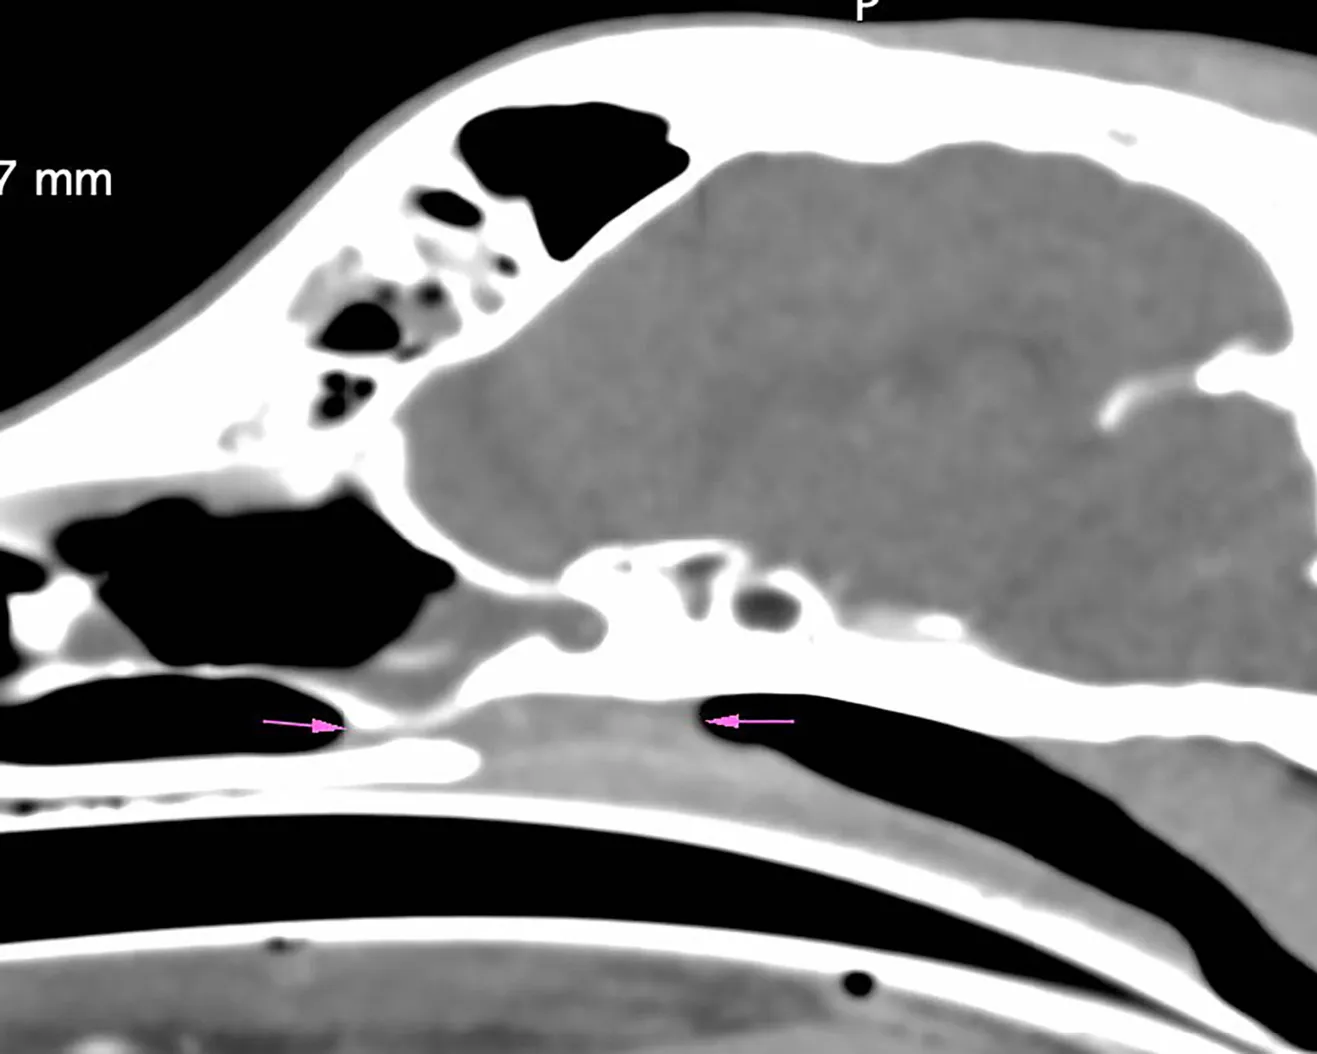

En la TC se apreciaron cambios óseos a nivel de las coanas, compatibles con una malformación congénita asociada o agravada por un posible proceso inflamatorio/infeccioso, que causaba una estenosis marcada de ambas coanas y del aspecto rostral de la nasofaringe (imágenes 1, 2 y 3). Entre los diagnósticos diferenciales de dicha estenosis de tejido blando se incluyeron: un proceso inflamatorio grave o un granuloma infeccioso (principalmente fúngico) sin que se pudiera descartar la presencia de una neoplasia nasofaríngea.

Tres semanas después, y antes de la sinuscopia por trepanación sinusal, se repitió una TC de cráneo y una rinoscopia de revisión (imagen 4), donde no se apreciaron cambios significativos. Se procedió a la trepanación de ambos senos frontales para la toma de muestras (cultivo bacteriano y fúngico) y la sinuscopia (imágenes 5 y 6), y se identificó una mayor cantidad de secreción en el seno izquierdo. No se detectaron estructuras fúngicas.